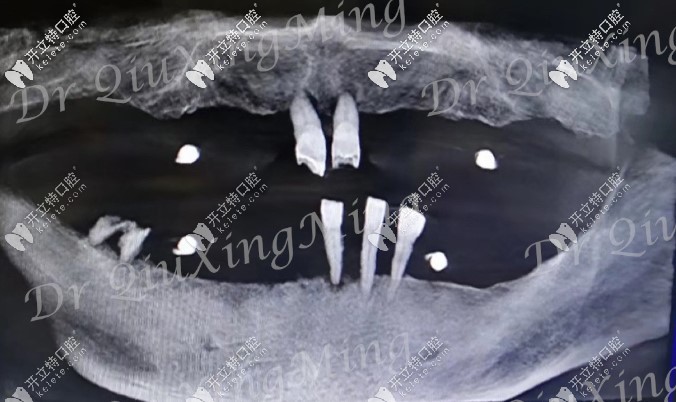

首先看下他的牙齒情況:嘴里還剩下5顆牙,還有2顆殘根,邱醫(yī)生建議全部拔掉,因?yàn)槟?顆牙也已經(jīng)松動(dòng)了,沒有保留的必要。

檢查顯示他的牙槽骨有部分吸收,一般的種植手術(shù)是需要植骨的,但邱醫(yī)生給他用的是all-on-4種植技術(shù),不用植骨,還可以選擇即拔即種的修復(fù)方式。